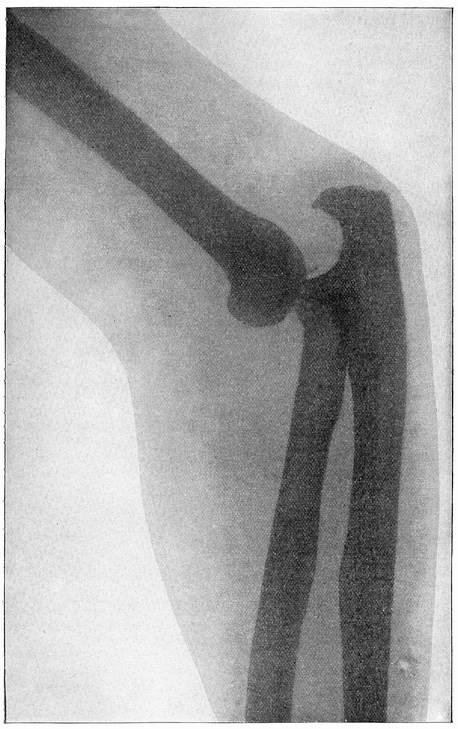

| X-Ray Photograph of a Compound Fracture of Forearm | 628 |

| X-Ray Picture of a Dislocated Elbow. Full page | 629xviii |